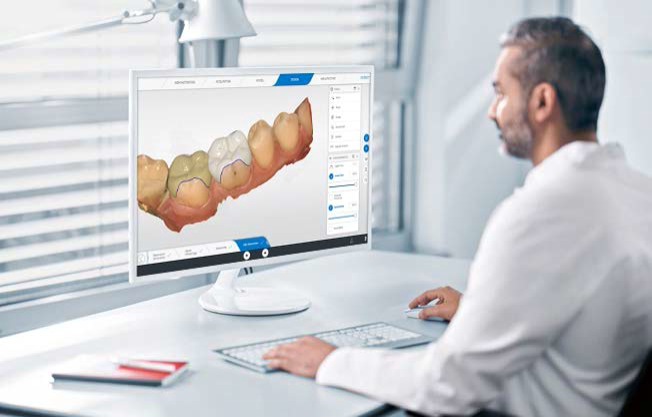

Com a chegada da nova geração ao corpo clínico, a clínica deu um salto tecnológico e consolidou sua expertise em odontologia digital, oferecendo precisão, conforto e resultados superiores.

No COES, a tecnologia, conforto e resultados são parte essencial do cuidado. Nosso fluxo de trabalho, totalmente digital, integra a tecnologia CAD/CAM, Chairside, através do uso de Scanner Intraoral, Software de Planejamento, Impressora 3D, Fresadora e Tomografia de Alta Resolução.

Planejamento Digital Completo

Simulações 3D em Tempo Real

Precisão Milimétrica em Cada Procedimento